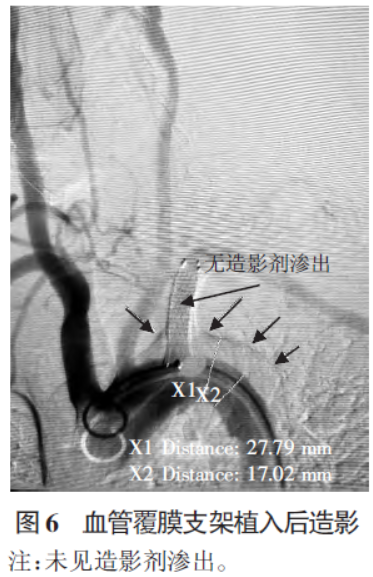

确认主动脉夹层形成,更换10F 动脉鞘,260 cm 加硬交换导丝置于左侧肱动脉,将血管覆膜支架(FVL10040)输送到位,确认位置后释放支架覆盖破口,支架前端不影响椎动脉起始部,末端平齐于锁骨下动脉起始部,再次造影无动脉造影剂持续渗出。间隔10 min 后再次行主动脉造影,锁骨下动脉血流正常,锁骨下动脉-胸主动脉夹层无进展改变,见图6。